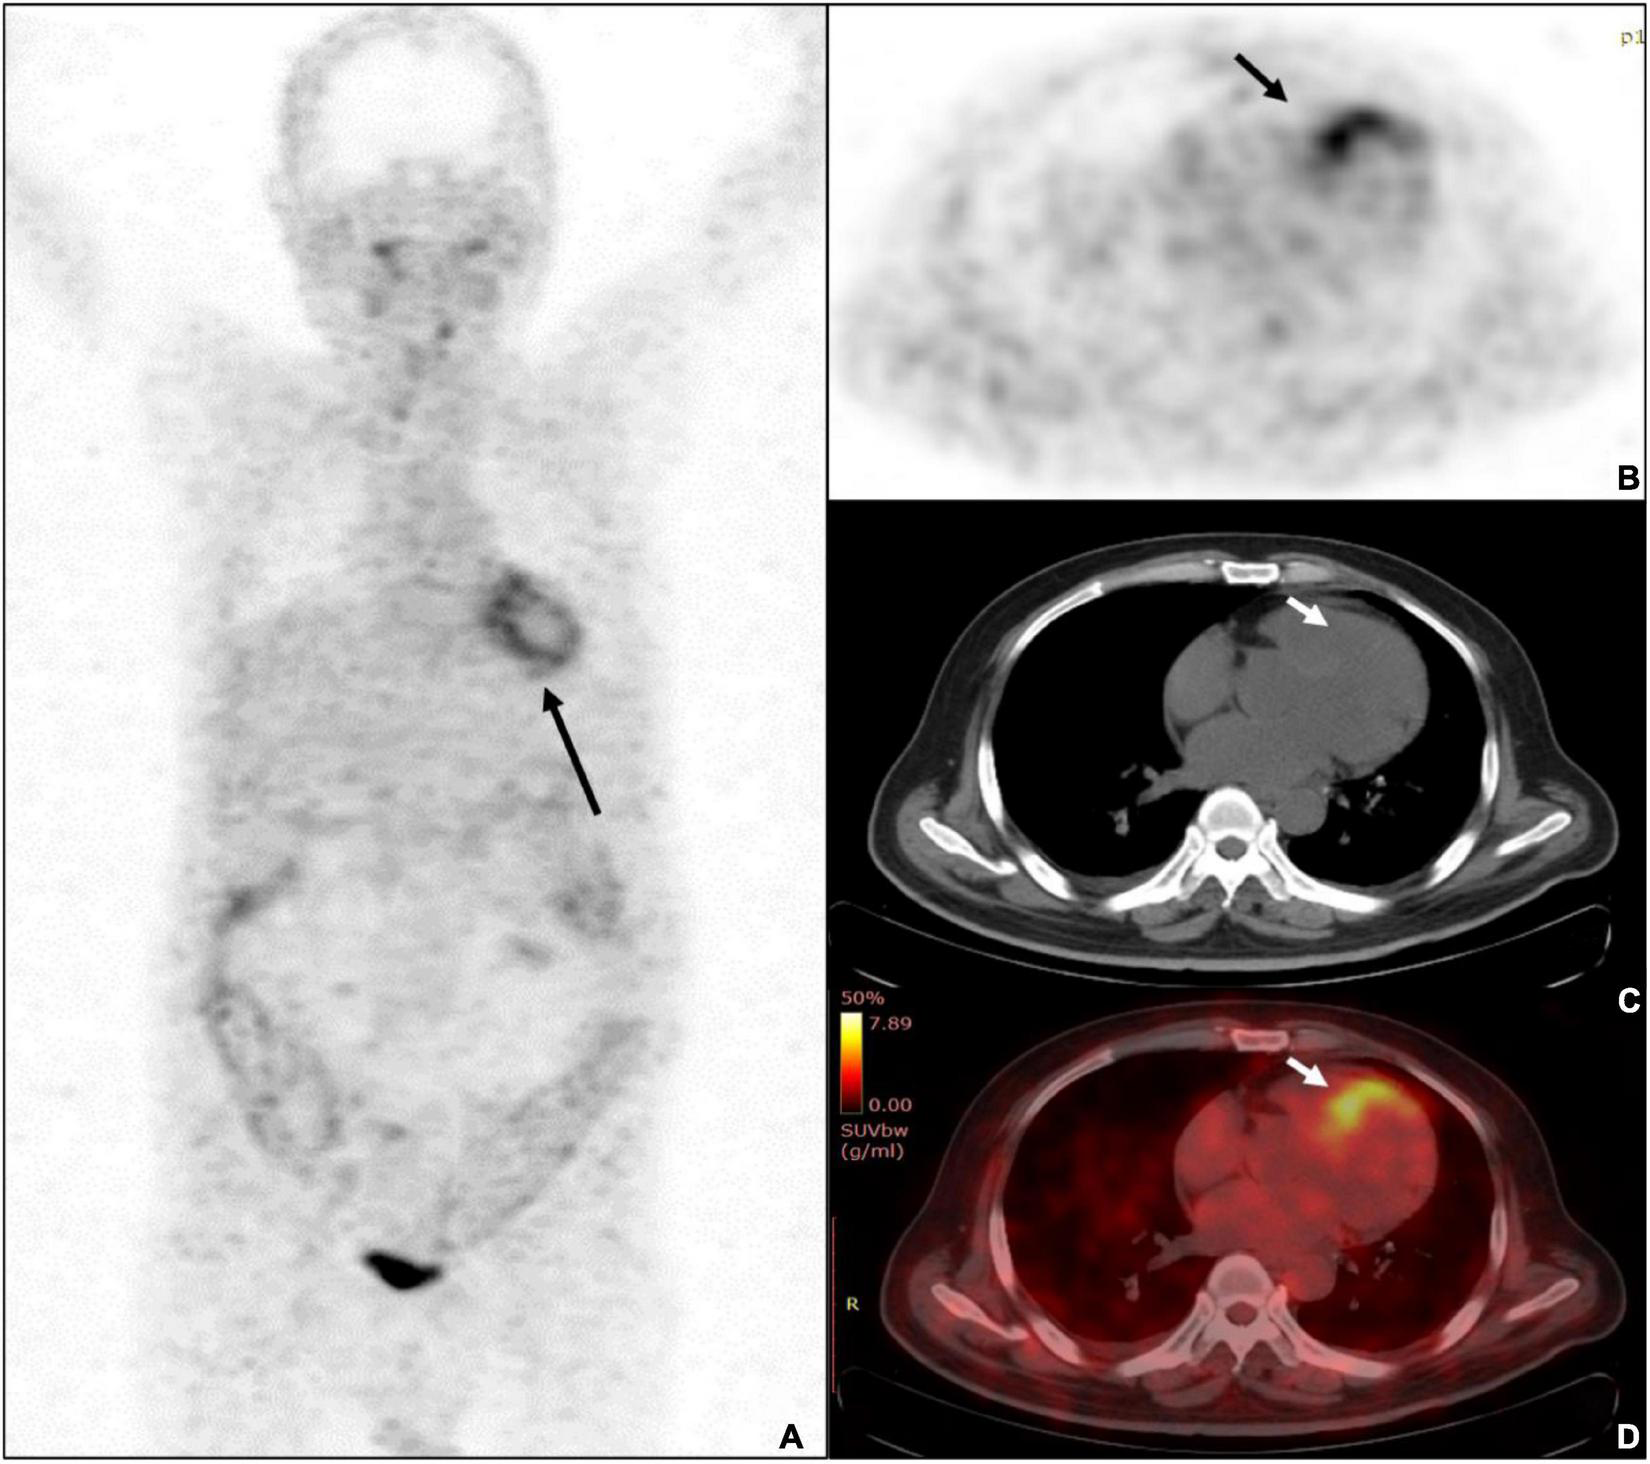

FIGURE 2

A 68-years-old male patient was diagnosed with ulcerative colitis and diabetes mellitus. (A) The whole-body MIP of Al18F-NOTA-FAPI-04 PET imaging demonstrated diffused uptake pattern in LV (black arrow) and diffused uptake with colons. (B) The PET imaging showed the highest uptake of SUVmax was 7.0 (black arrow). (C) Unfused CT image of the heart. (D) The fusion imaging showed the septal wall of prominent uptake of FAPI-04.